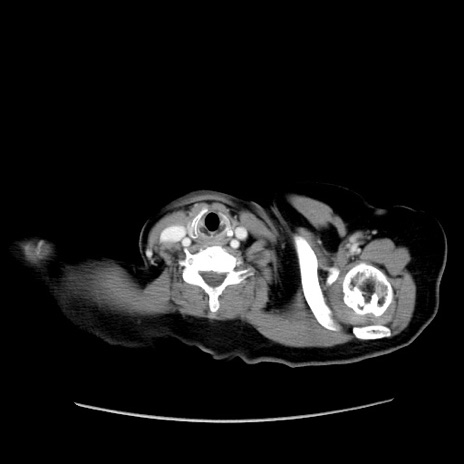

症例19(横断像)

【症例】80歳代女性

【主訴】下腹部痛

【現病歴】約8時間前より下腹部痛の出現あり、救急外来受診。

【既往歴】両側付属器切除

【身体所見】意識清明、下腹部正中に手術痕あり、その部位に一致して圧痛と反跳痛あり。腸蠕動音は亢進。

【データ】WBC 9300、CRP 0.15